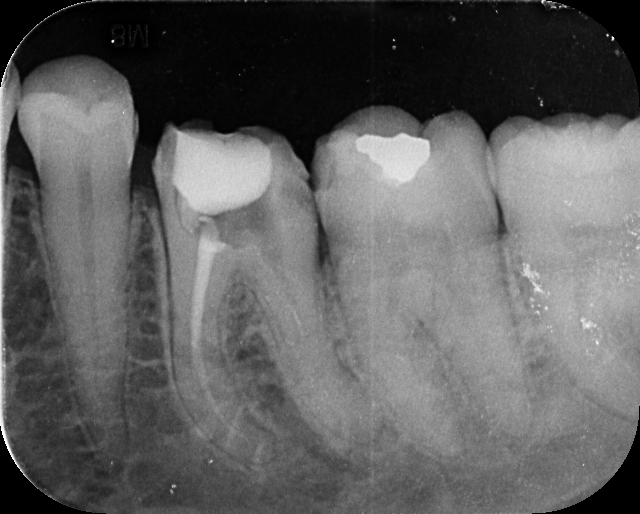

Our treatments are performed using advanced dental microscopes that magnify up to 25x- allowing us to identify previously hidden canals, fractures, or infected areas that standard tools may miss. This level of detail means faster, more accurate procedures and fewer surprises, giving your tooth the attention it truly deserves.